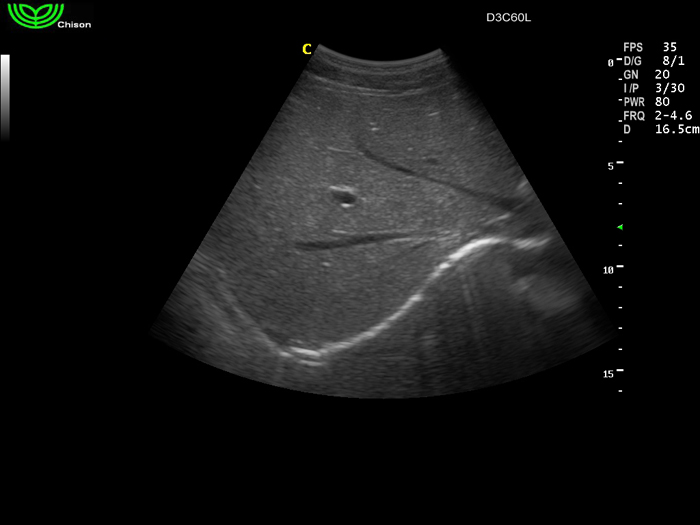

D3C60L 3.5МГц, конвексный.

2.0МГц - 5.8 МГц. Применения: абдомиальное обследование, акушерство, гинекология, обследование районной блокады нерва, осуществление и управление биопсией. |